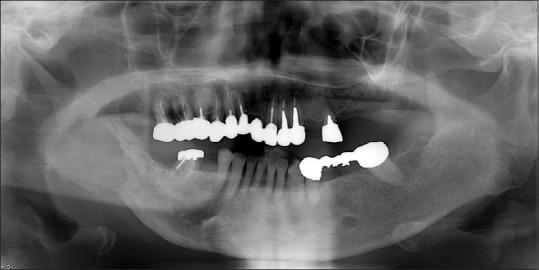

Neurofibromatosis type 1 (NF1) was first described in 1882 as a hamartomatous disorder of neural crest derivation. We present the imaging of a 65-year-old woman with NF1. Computed tomography revealed that there were three major findings presented: skeletal deformity, an area of fat (probably related to mesodermal dysplasia), and benign neoplasm within the masticator space. Moreover, masticatory muscles were hypoplastic.

1型神经纤维瘤病(NF1)于1882年首次被描述为一种源于神经嵴的错构瘤性疾病。我们展示了一名65岁NF1女性患者的影像学表现。计算机断层扫描显示有三个主要表现:骨骼畸形、一个脂肪区域(可能与中胚层发育异常有关)以及咀嚼肌间隙内的良性肿瘤。此外,咀嚼肌发育不全。